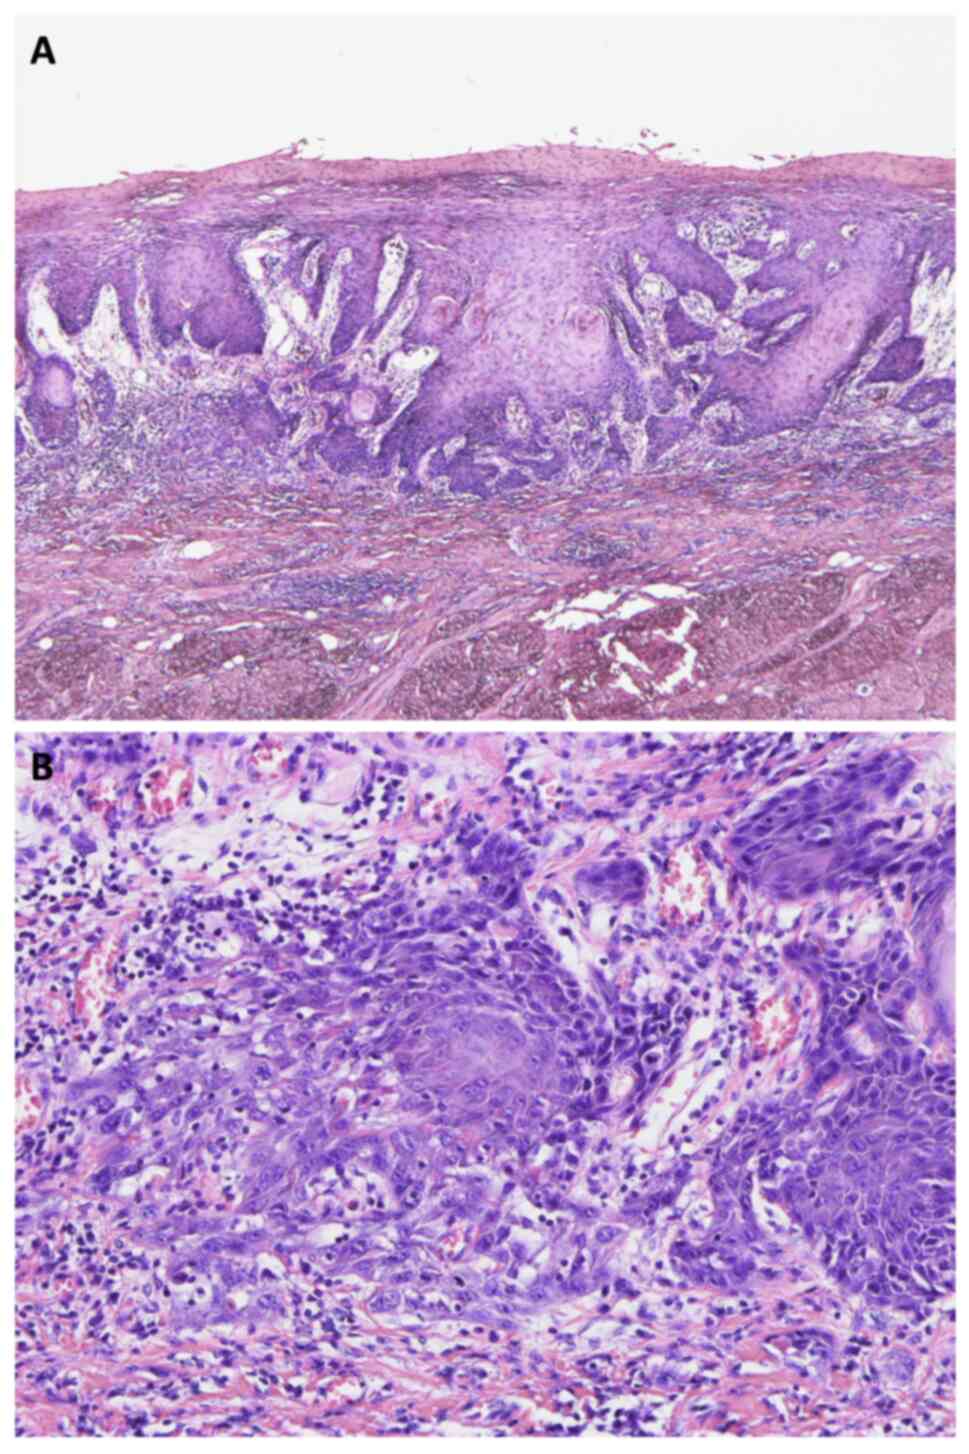

Contrast-enhanced computed tomography (CT) confirmed a shallow enhancing lesion in the left tongue, and the left submandibular and upper internal jugular lymph nodes were also enlarged (Fig. 2A-C). Blood tests revealed mild leukocytosis (WBC: 10,500/µl) with 75% neutrophils and a slight increase in C-reactive protein (CRP: 0.6 mg/dl). Liver and renal function tests were within normal limits. A biopsy of the tongue ulcer was performed, and histopathological examination revealed typical features of HSV infection, including multinucleation, molding of nuclear contours, and intranuclear inclusions, which were positive for HSV1 by immunohistochemistry (Fig. 3A and B). Serological testing showed elevated HSV IgM levels and low HSV IgG levels, suggesting primary HSV infection. The patient's clinical symptoms subsided within 1 week without antiviral treatment, and a follow-up examination demonstrated increasing HSV IgG titers.

Figure 3.

Histopathological findings of the first biopsy. (A) Histopathological examination showing multinucleation, molding of nuclear contours, and intranuclear inclusions, consistent with HSV infection. (B) Squamous cells were positive for HSV by immunohistochemistry. Magnification: (A) ×40 and (B) ×100. HSV, herpes simplex virus.

Before resection, Lugol's iodine staining was performed to differentiate the lesion. Unstained area corresponding to the leukoplakia and erythroplakia were identified (Fig. 6). A partial glossectomy was performed with a 10-mm safety margin. Histopathological analysis of the resected specimen confirmed squamous cell carcinoma (pT1N0M0) with tumor-free margins (Fig. 7A and B). Notably, no HSV-infected cells were detected in the resected specimen.

Figure 7.

Histopathological images of the resected specimen. Squamous cell carcinoma (pT1N0M0) with tumor-free margins was confirmed, and no herpes simplex virus-infected cells were detected. Magnification: (A) ×40 and (B) ×200.